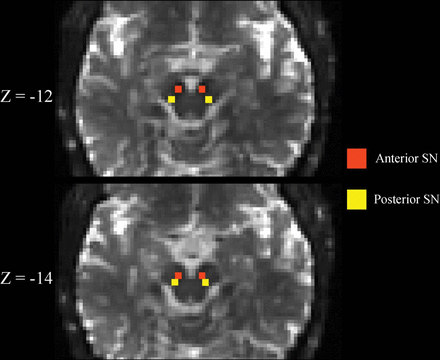

SN ROIs were drawn by one of the blinded authors (N.B.) as previously described.11 Briefly, the b=0 image was linearly registered with 12 df to a T2-weighted MNI space image with 2-mm3 isotropic voxels.25 Next, left and right hemisphere anterior and posterior SN ROIs were drawn separately on each b=0 image after transformation into MNI space. Each ROI consisted of a 2 × 2 mm square placed on 2 consecutive slices, for a total of eight 2 × 2 × 2 mm3 voxels. The superior slice for the SN ROI placement was chosen just inferior to the red nucleus where the red nucleus was either barely or no longer visible. Anterior and pSN ROIs were placed in the area of hypointense signal on the b=0 image corresponding to the SN (Fig 1). Such SN ROI placement is also consistent with placement guided by neuromelanin-sensitive imaging.5 Finally, the DTI-derived maps were resampled into MNI space with trilinear interpolation using the b=0 transformation matrix, and quantitative measures were extracted from the SN ROIs. Other exploratory ROIs were delineated as previously described.19,21,23 The MR imaging scanner underwent no hardware or software upgrades during the study.

Substantia nigra ROIs. Representative b=0 s/mm2 images linearly registered to the MNI atlas are shown demonstrating the placement of the substantia nigra ROIs. Z-coordinates refer to the slice shown in MNI space. See the “Materials and Methods” section for a more detailed description of how ROIs were placed.